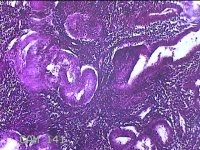

宫腔赘生物

性别

女

年龄

50岁

临床诊断

异常子宫出血 子宫腔赘生物待查 子宫肌瘤 疤痕子宫

一般病史

不规则流血25天,增多7天。

标本名称

大体所见

灰白粉红色肿物1x0.8x0.2cm两个,表面光滑。

子宫内膜增生症。制片欠佳。

增殖性子宫内膜,局部呈息肉改变